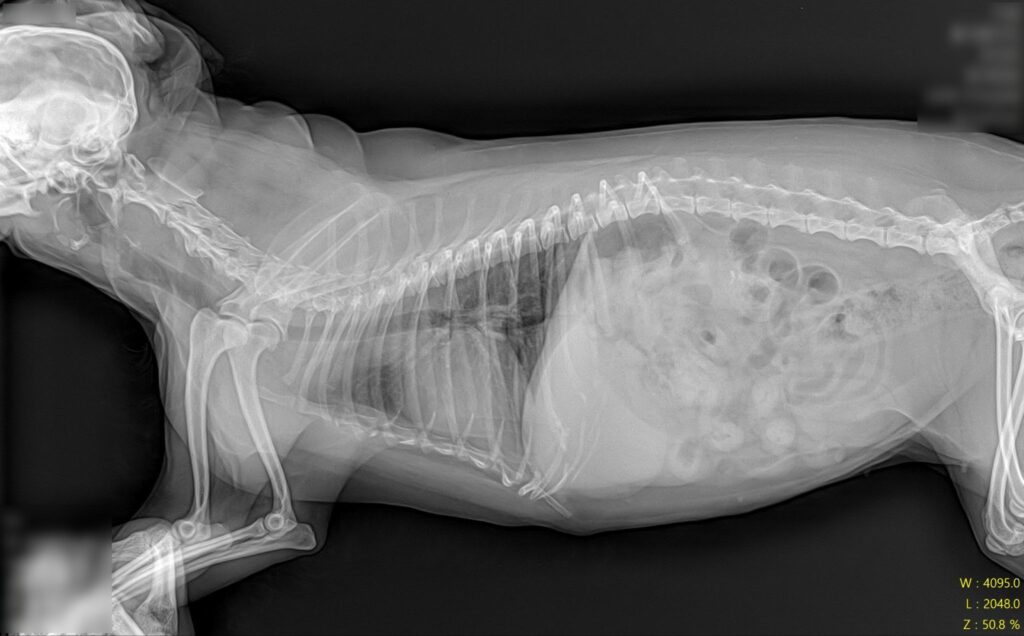

수술 전 방사선 검사 / 출처: 라온동물메디컬센터

정형학적 검사와 방사선 영상 검사를 진행한 결과, 우측 슬관절의 불안정성과 함께 전방십자인대 단열(CCL rupture) 소견이 확인되었습니다. 기존 슬개골 수술 부위의 임플란트 상태는 양호했으나, 슬관절 주변으로 골관절염 진행과 관절 삼출액 소견이 동반되어 있었습니다.